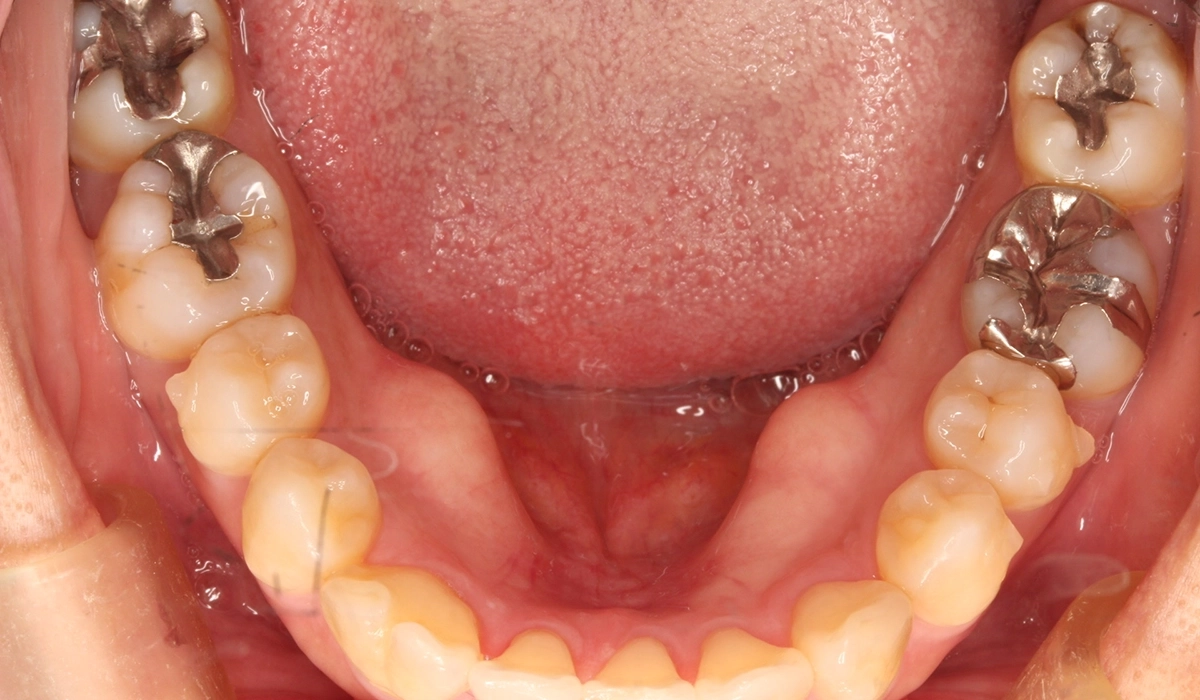

術前:下顎

術後:下顎